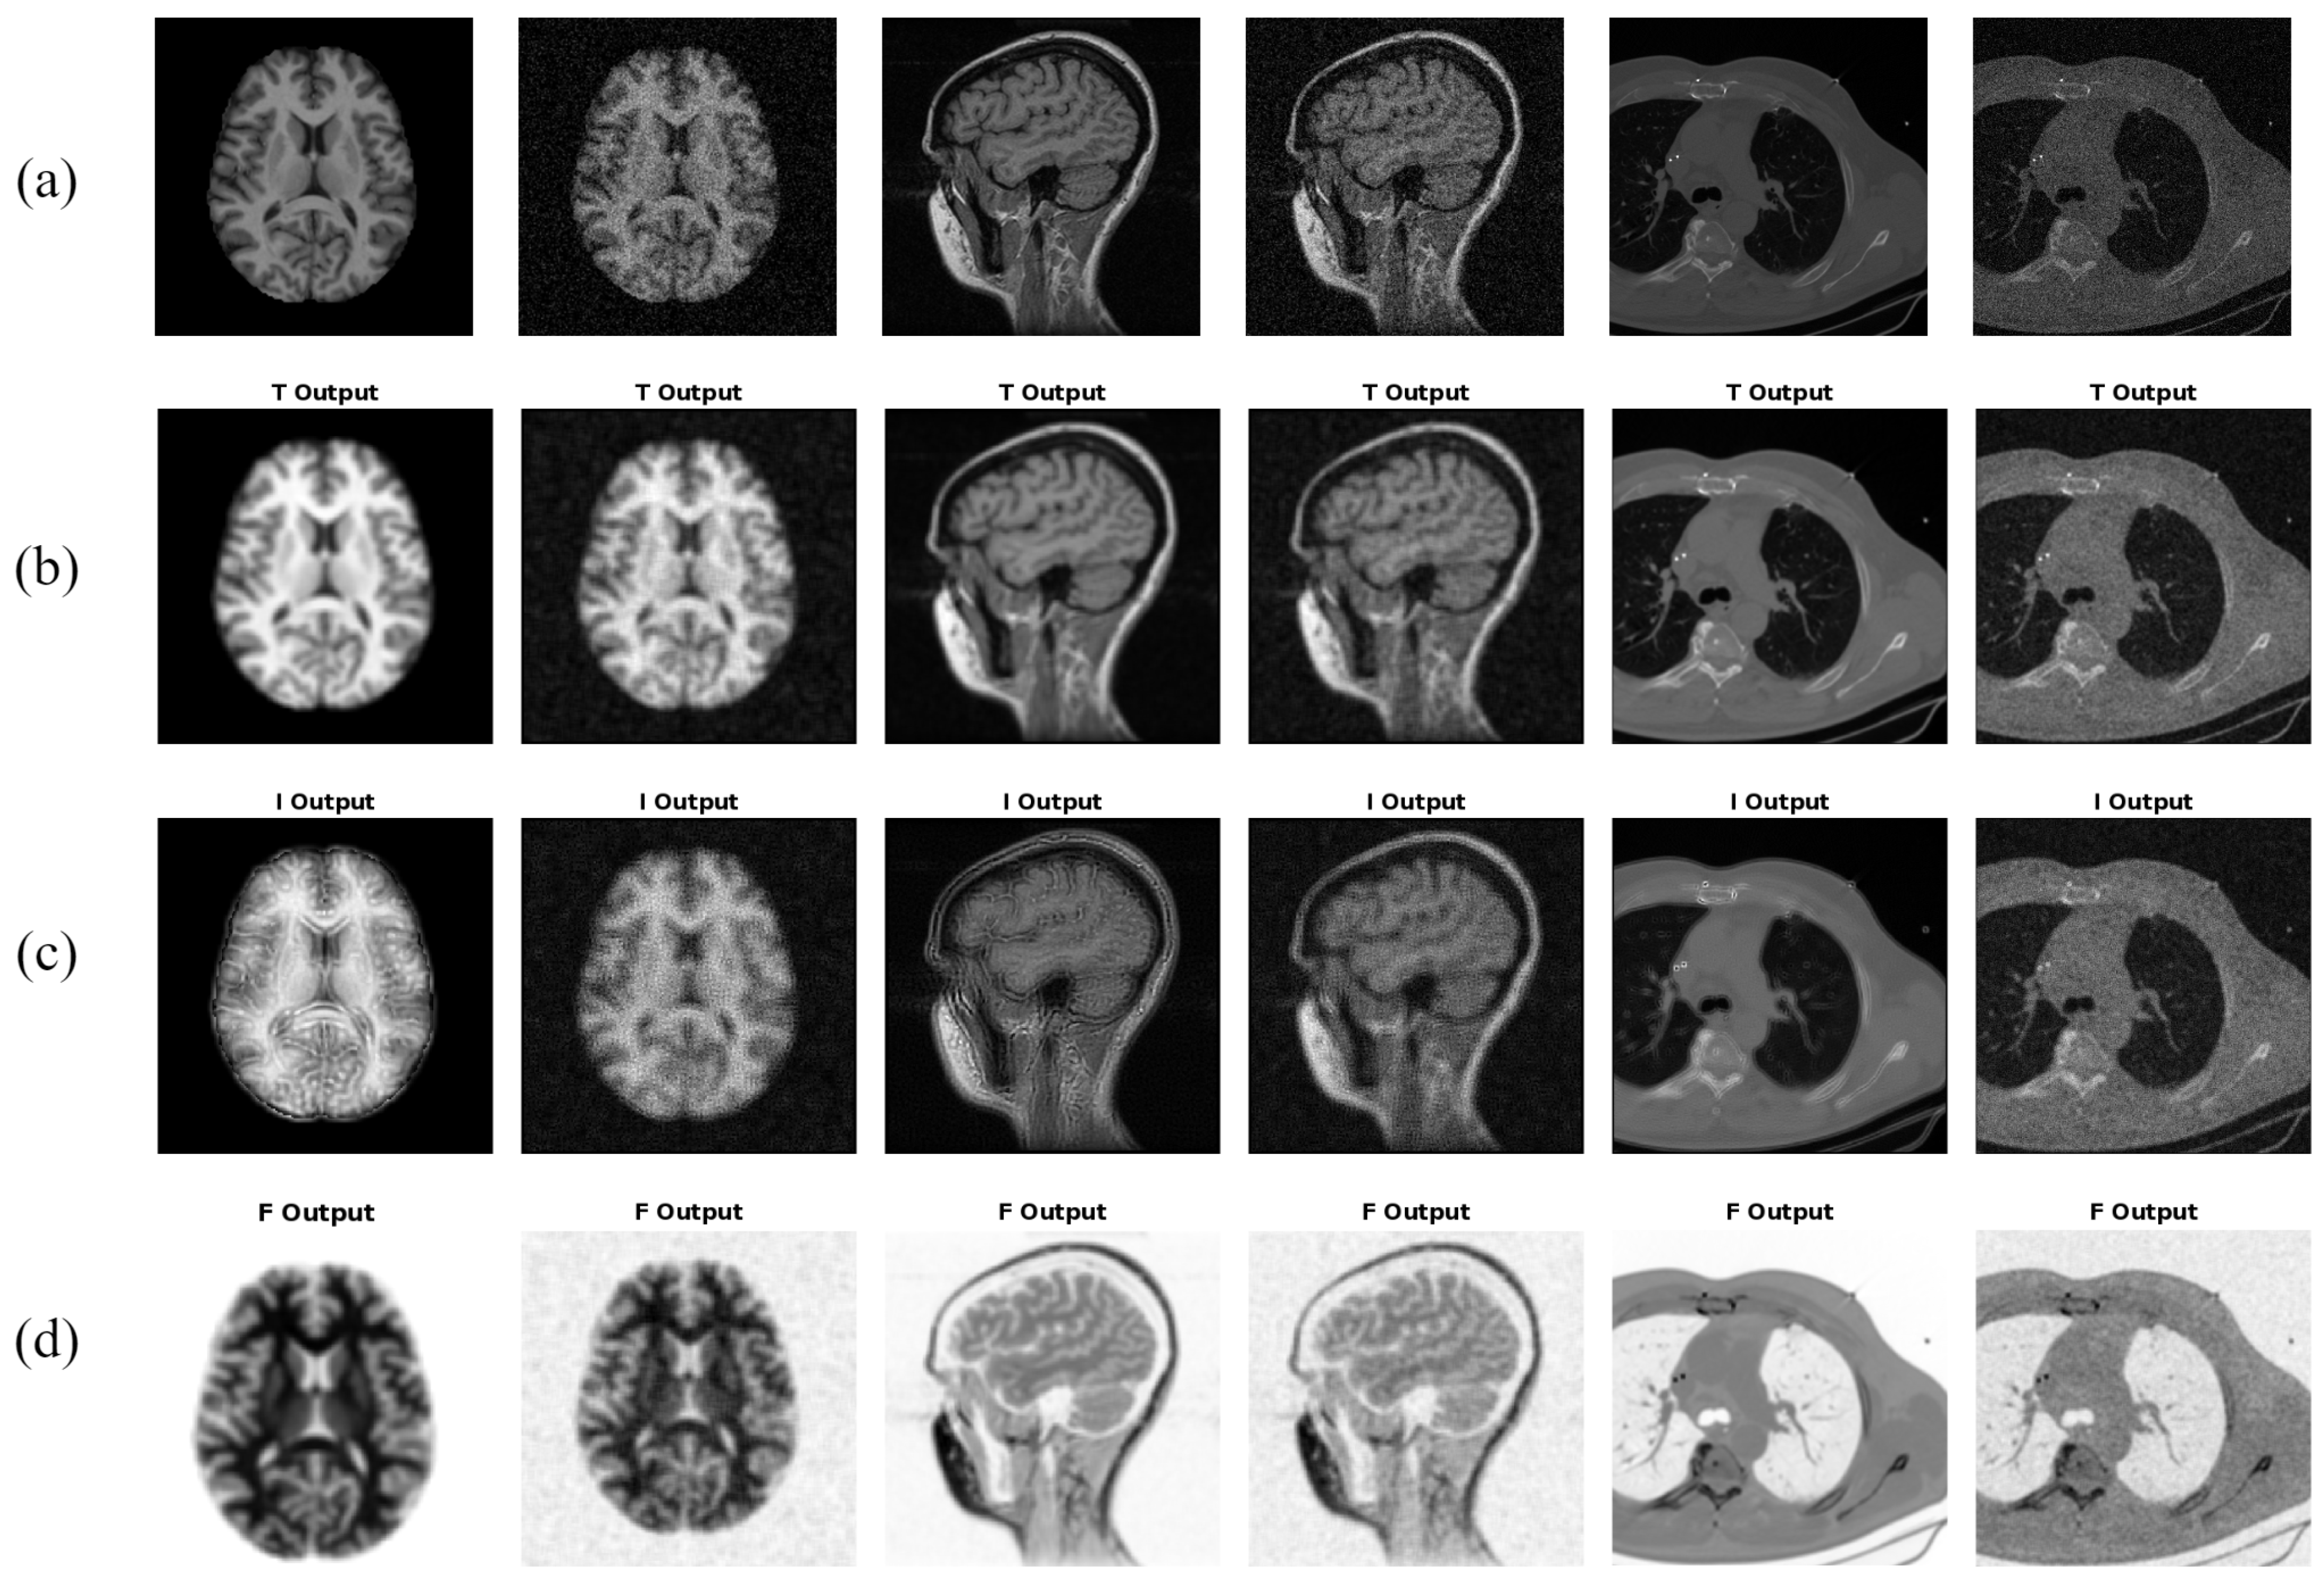

- A new approach, , is presented that extracts texture features from all three neutrosophic images, i.e., truth (T), indeterminacy (I), and falsity (F). The texture features from each of the T, I, and F images are appended together to form the final feature vector for .

- Firstly, the medical image is transformed to the neutrosophic domain, such that for every input medical image, we obtain three neutrosophic images, i.e., truth (T), indeterminacy (I), and falsity (F).

2.1. Construction of Neutrosophic Images